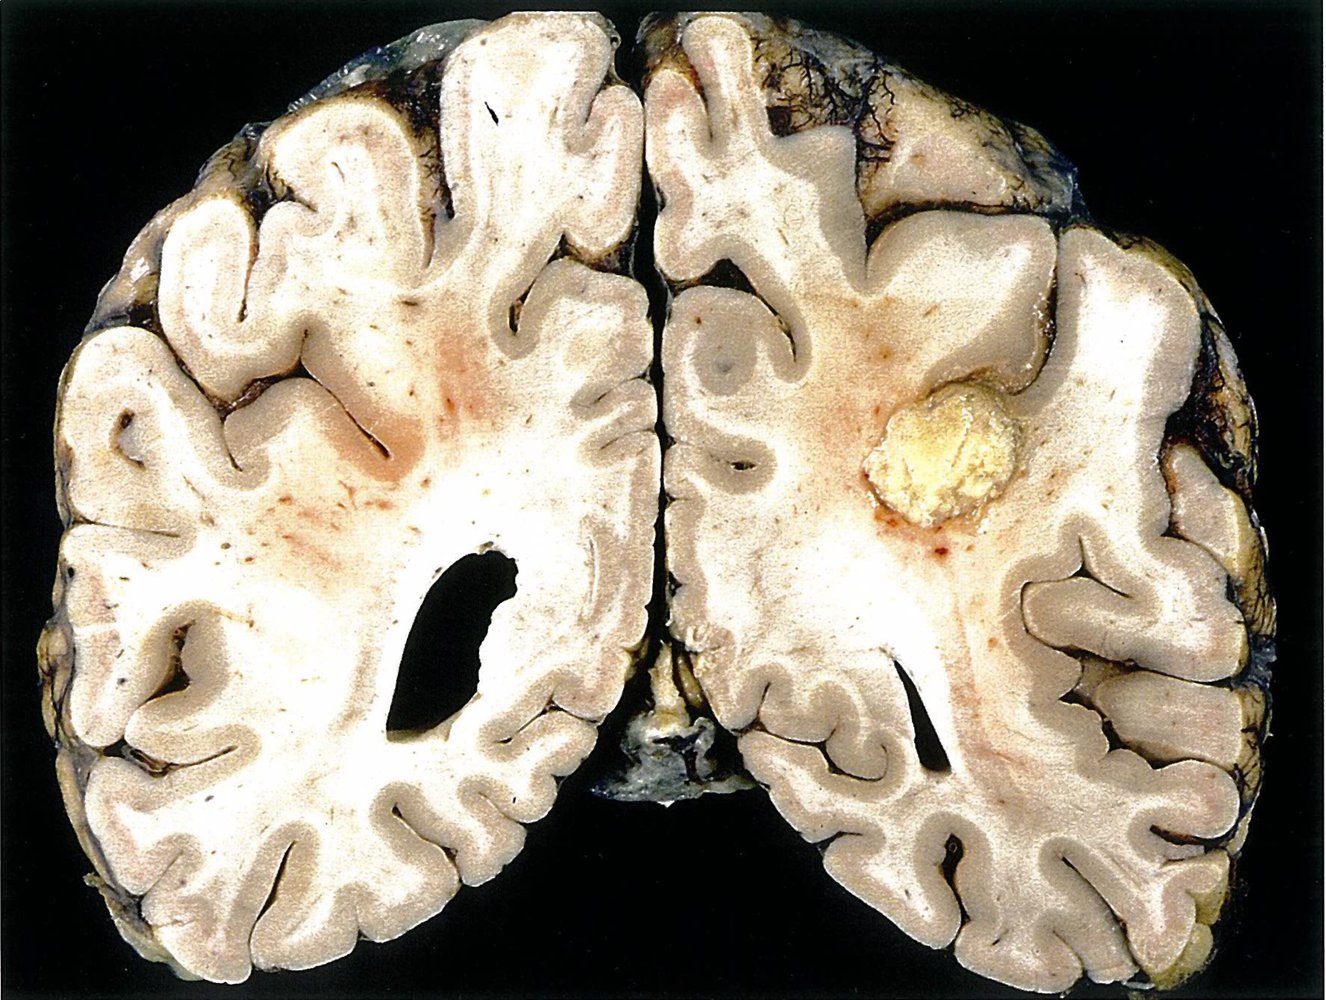

• Manifestations include brain abscess, meningitis, ventriculitis, and/or cerebral venous thrombosis.

• CT and MRI brain with contrast (for suspected CNS Aspergillus infection): [10]

• Ring-enhancing lesions consistent with abscess formation